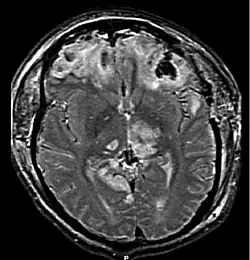

Broca y Wernicke fueron pioneros en el estudio de los trastornos del lenguaje con el objetivo de localizar las áreas cerebrales específicamente relacionadas con el lenguaje. Las primeras investigaciones revelaron que las áreas de las funciones del lenguaje se sitúan en el hemisferio izquierdo (lateralización del lenguaje), próximas a la unión de los lóbulos temporal, frontal y parietal. Las lesiones en el área de Broca, situada en la circunvolución inferior del lóbulo frontal izquierdo, provocan trastornos del lenguaje, motores y expresivos. Las lesiones en el área de Wernicke, situada en la circunvolución superior del lóbulo temporal izquierdo, producen trastornos de tipo receptivo o sensorial, es decir, que afectan a la comprensión del lenguaje.

El origen de los trastornos del lenguaje puede ser variado. En general, cuándo la causa puede localizarse en una lesión o disfunción cerebral o del sistema nervioso, se emplea el término orgánico, y, si no es posible descubrir causas similares a las mencionadas, se consideran trastornos funcionales (es necesario mencionar que pueden ser causa de trastorno funcional tumores cerebrales, lesiones obstétricas, enfermedades infecciosas del tipo meningitis, heridas craneales, etc.).[6]